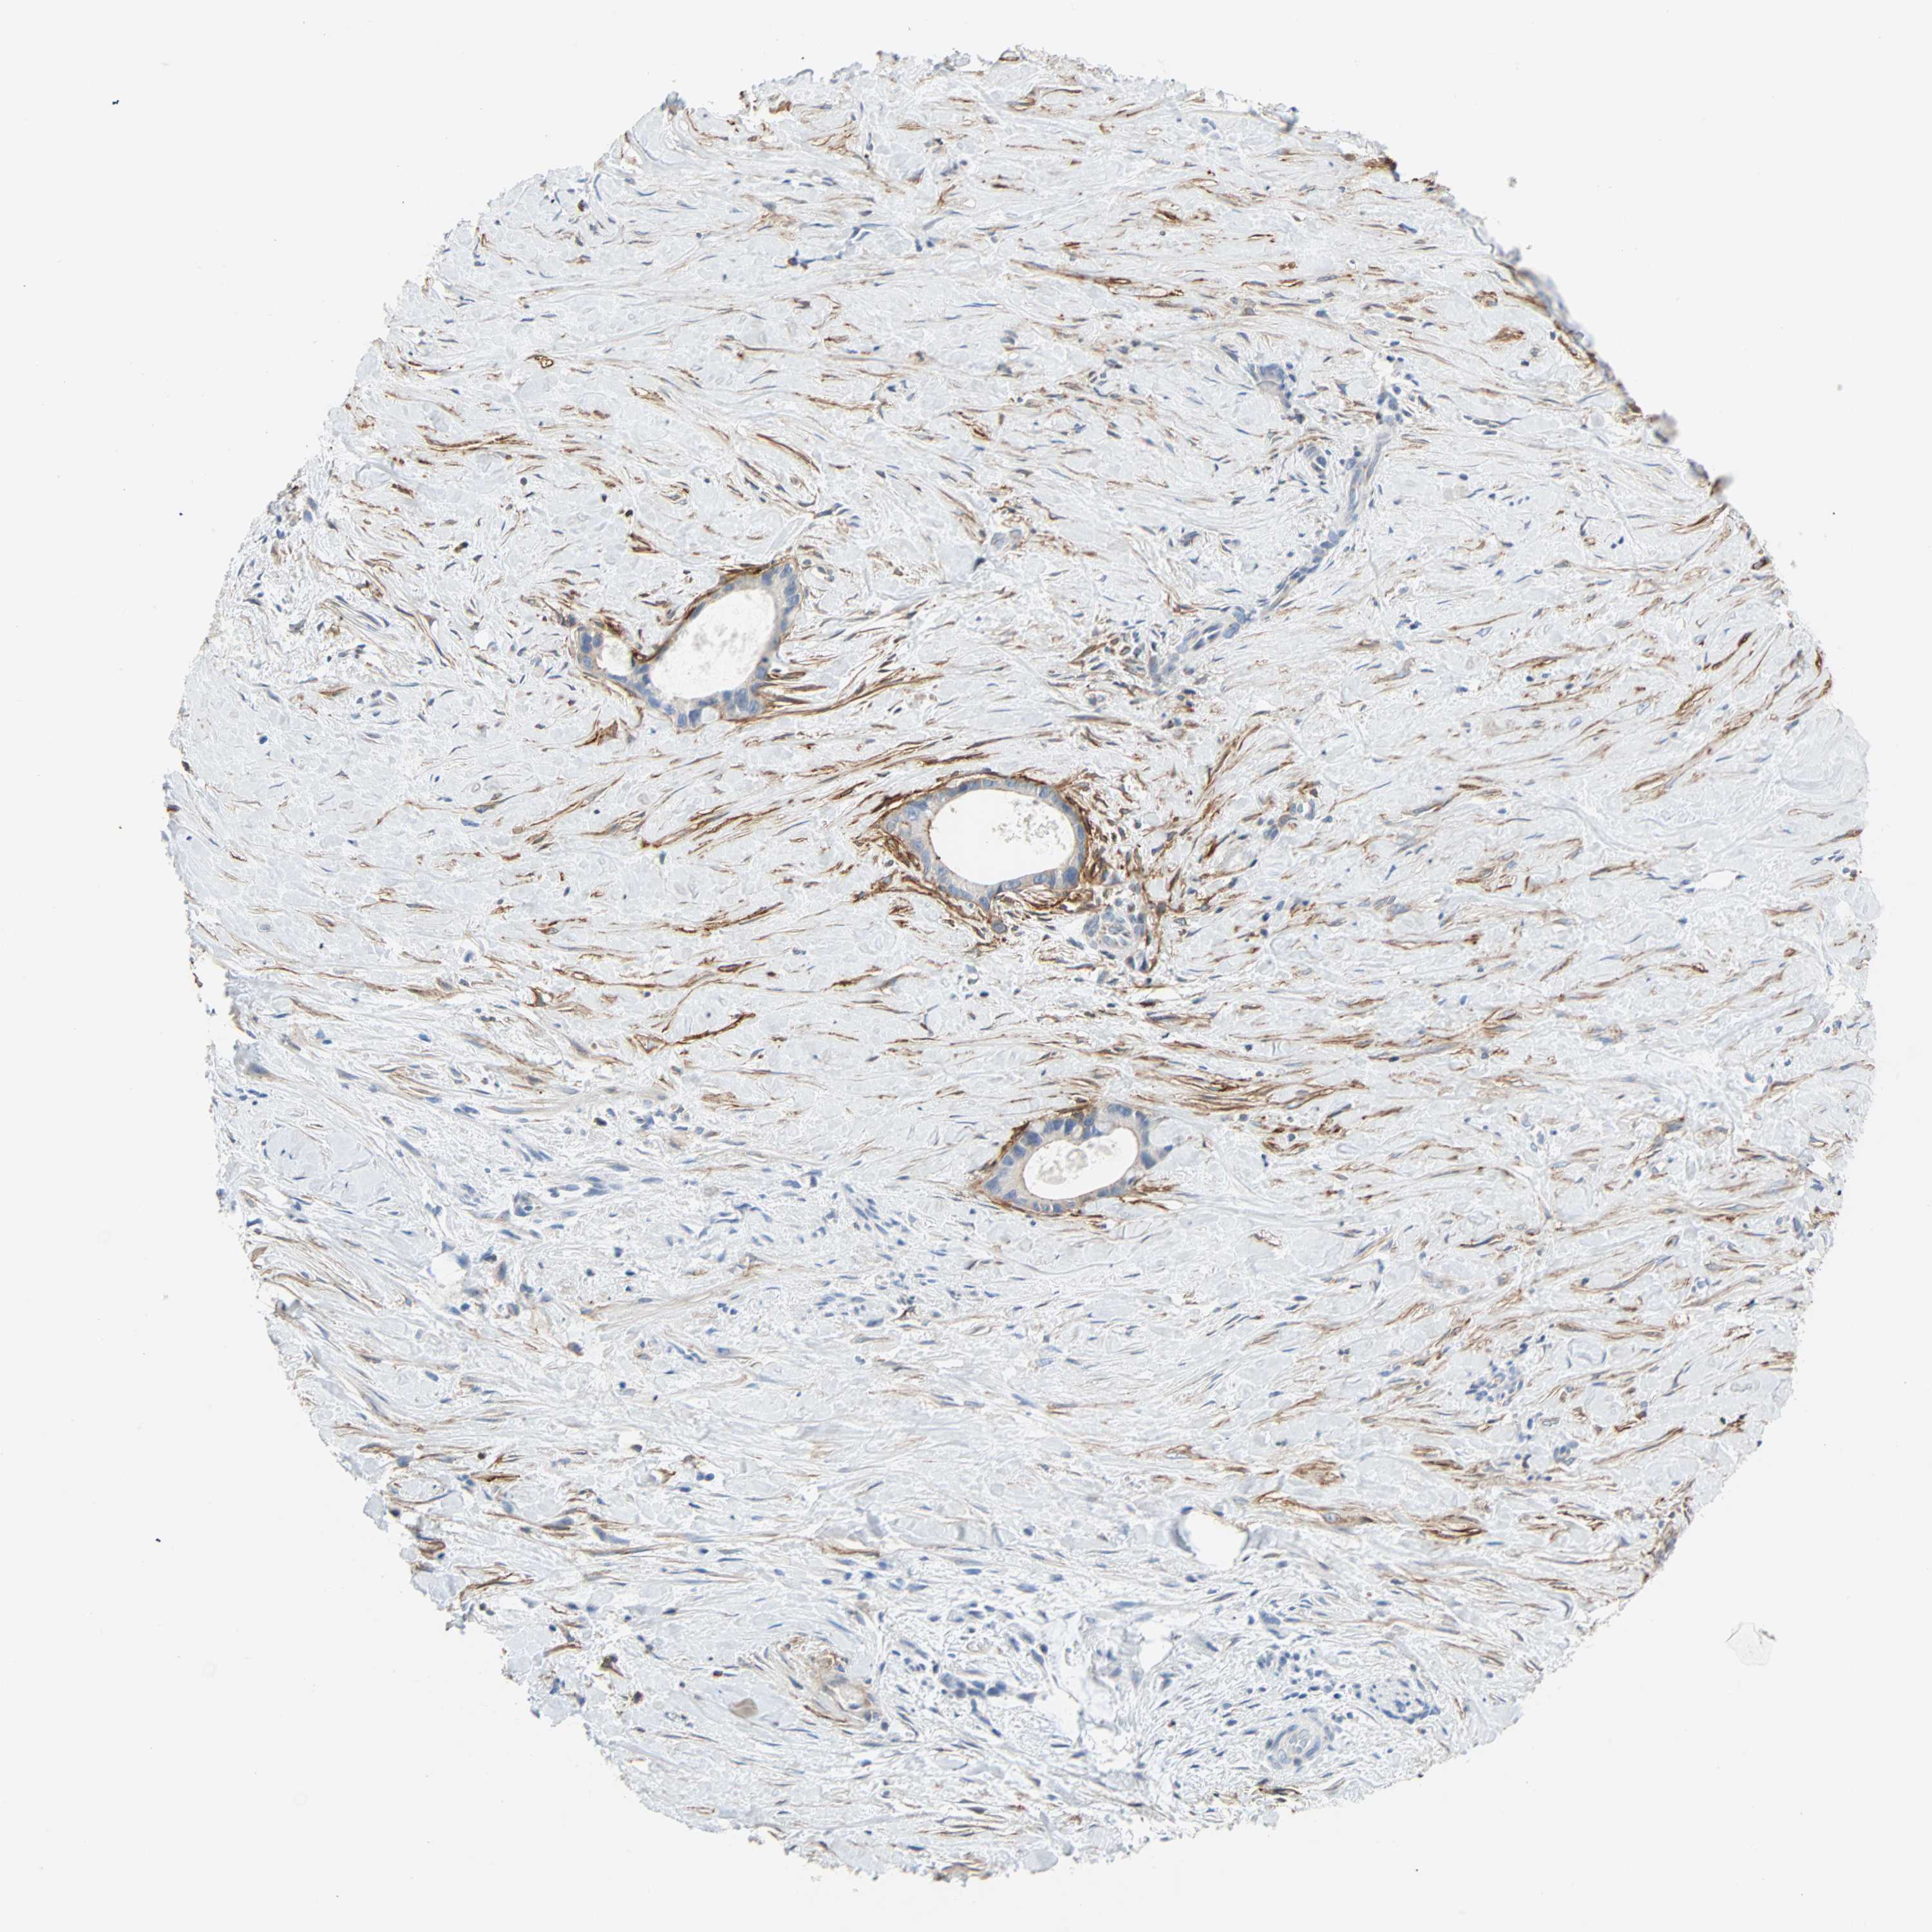

LIVER CANCER - Protein expressioni

A mouse-over function shows sample information and annotation data. Click on an image to view it in a full screen mode. Samples can be filtered based on level of antibody staining by selecting one or several of the following categories: high, medium, low and not detected. The assay and annotation is described here.

Note that samples used for immunohistochemistry by the Human Protein Atlas do not correspond to samples in the TCGA dataset.

Antibody stainingi

Antibody staining in the annotated cell types in the current human tissue is reported as not detected, low, medium, or high, based on conventional immunohistochemistry profiling in selected tissues. This score is based on the combination of the staining intensity and fraction of stained cells.

Each image is clickable and will lead to virtual microscopy that enables deeper exploration of all samples and also displays staining intensity scores, fraction scores and subcellular localization as well as patient and tissue information for each sample.

Antibody HPA007534

Antibody CAB008376

Staining

High

Medium

Low

Not detected

Intensity

Strong

Moderate

Weak

Negative

Quantity

>75%

75%-25%

<25%

None

Location

Nuclear

Cytoplasmic/membranous

Cytoplasmic/membranous,nuclear

Cholangiocarcinoma

Carcinoma, Hepatocellular, NOS